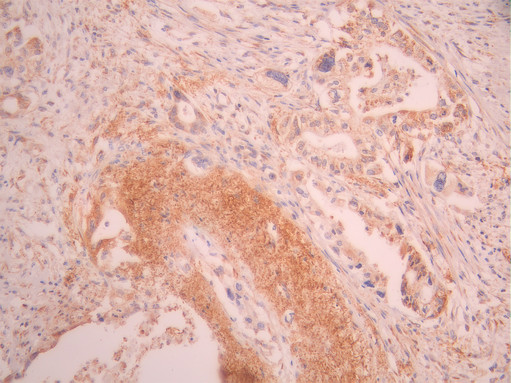

• IHC image of CSB-RA270924A0HU diluted at 1:100 and staining in paraffin-embedded human pancreatic cancer performed on a Leica BondTM system. After dewaxing and hydration, antigen retrieval was mediated by high pressure in a citrate buffer (pH 6.0). Section was blocked with 10% normal goat serum 30min at RT. Then primary antibody (1% BSA) was incubated at 4°C overnight. The primary is detected by a Goat anti-rabbit polymer IgG labeled by HRP and visualized using 0.05% DAB.